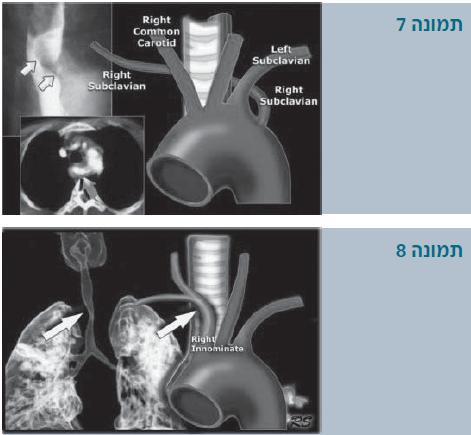

קשת אבי-עורקים ימנית

קשת אבי-עורקים ימנית עם עורק תת-בריחי שמאלי לקוי ורצועה של הצינור העורקני (תמונה 4):

במקרה זה מהקשת הימנית יוצאים ענפים בסדר הבא:

- ראשון יוצא עורק התרדמה השמאלי

- שני יוצא עורק התרדמה הימני

- שלישי יוצא העורק התת בריחי הימני

- רביעי יוצא העורק התת בריחי השמאלי. העורק התת-בריחי יוצא, אם כן, אחרון בשורה, מאחורי הוושט והקנה.

- לרוב, משלימה את הטבעת רצועה של הצינור העורקני, שמחבר בין עורק הריאה ובין אבי העורקים היורד או העורק התת-בריחי השמאלי. על ידי כך הוא משלים מעין טבעת שלמה (תמונה 3א).

לעתים צורה זו מלווה בבליטה בבסיס של העורק התת-בריחי השמאלי הלקוי, כפי שמתואר בתמונה 4א. בליטה זו נקראת הסעיף על שם קומרל (Kommerell' diverticulum). אם סעיף כזה נמצא בניתוח, ברוב המקרים נוהגים לכרות אותו: תוארו מקרים בהם אם מסתפקים בניתוק הרצועה של הצינור העורקני, הסעיף יכול עדיין ללחץ על הוושט. כמו כן, תוארו התפתחות מפרצות ואף דימום מסעיף הזה.